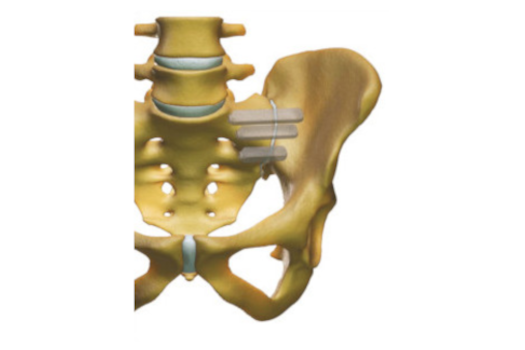

Instabilité et douleurs Sacro-iliaques chroniques

Présentation de l’articulation Sacro-iliaque

Diagnostic et symptômes articulaires SI

Traitement des douleurs d'instabilité sacro-iliaque

Arthrodèse Sacro-Iliaque

Chirurgie Mini-invasive de stabilisation de l'A.S.I.